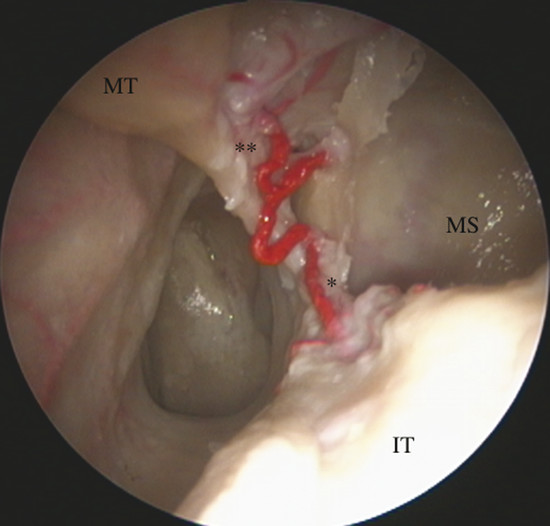

It gives off two main branches, the posterior lateral nasal artery (PLNA) and the posterior septal artery (PSA), 1 , 2 which can be divided into one or two trunks medial to the ethmoidal crest, before or after crossing the sphenopalatine foramen. It is rarely possible to identify more than two trunks. 1 , 3 The PLNA supplies the region of the lateral nasal wall giving off branches to the inferior turbinate (inferior turbinate artery), middle turbinate (middle turbinate artery), mucosa of the fontanelle, and to the mucosa of the maxillary sinus 4 (Fig. 3‑3, Fig. 3‑4). In approximately 20% of cases this artery supplies the superior turbinate. 5 The inferior turbinate artery enters a bony canal and runs anteriorly along the turbinate. It usually gives off two terminal branches, within or adjacent to the bone, supplying the mucosa of the turbinate (Fig. 3‑5). The artery gives off several small vessels to the maxillary sinus and to the ethmoidal complex. The middle turbinate artery gives off several branches, some of which run along the medial surface of the turbinate whereas the other branches supply the lateral turbinate surface and anterior ethmoidal complex (see Fig. 3‑3).